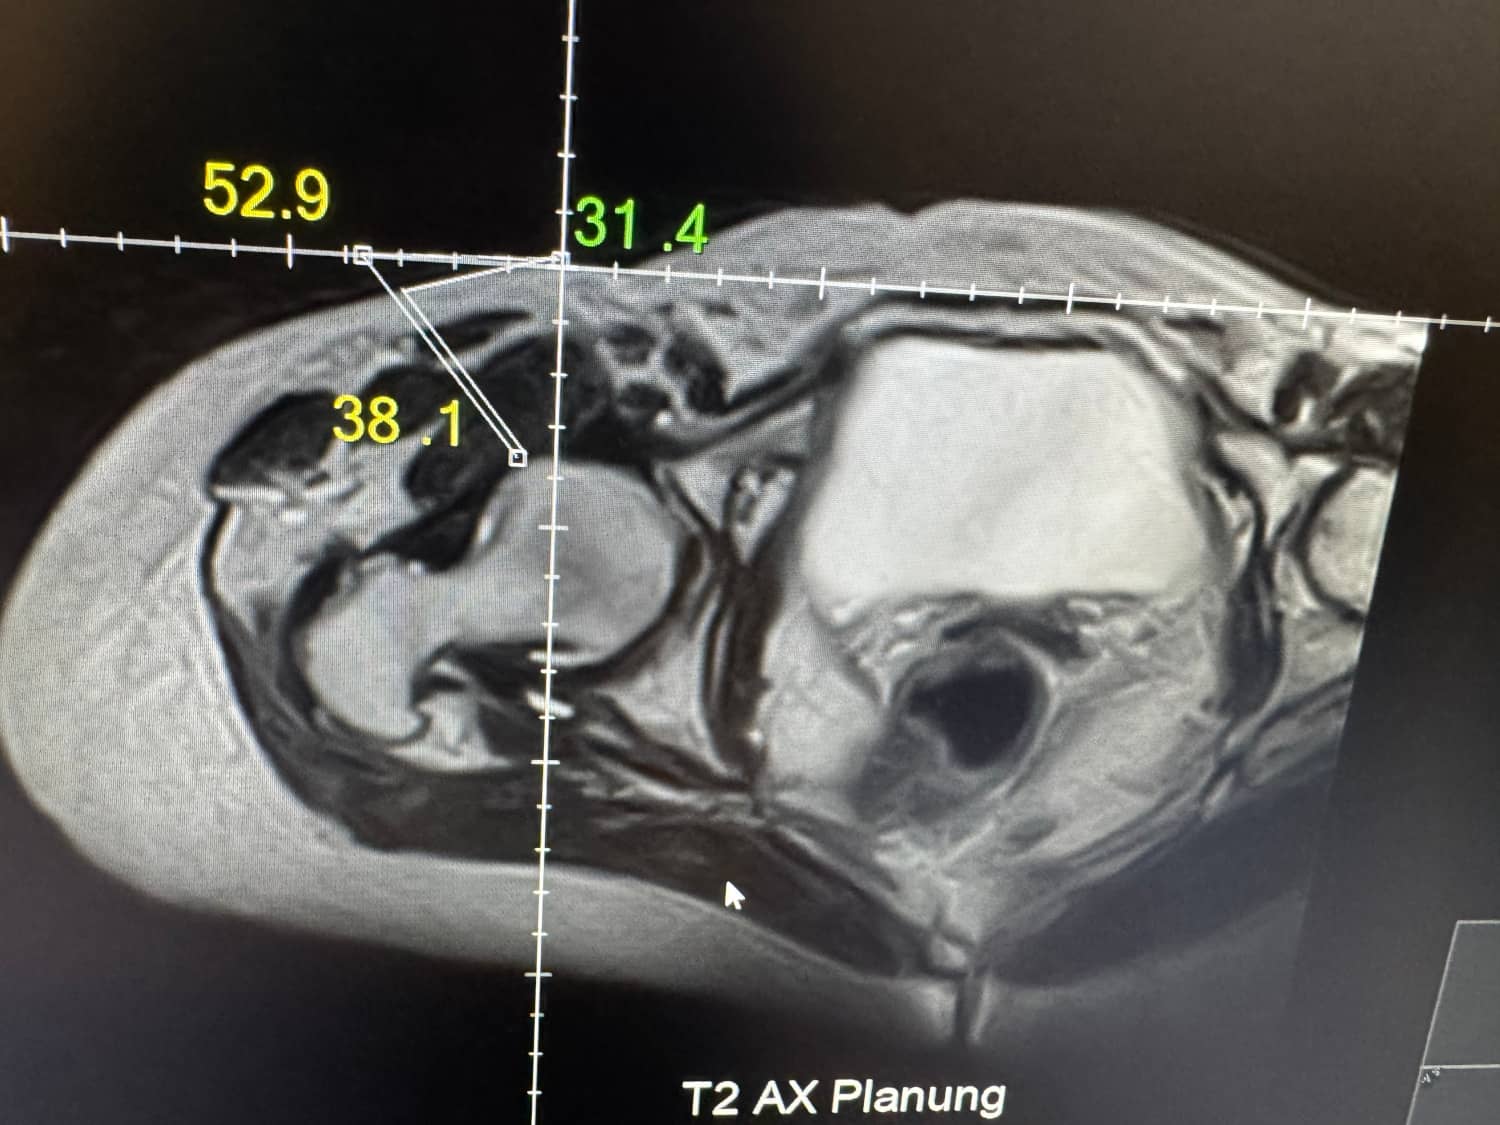

AMT-Behandlung am Beispiel Hüftgelenk: